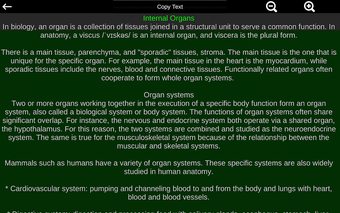

此应用程序显示人体器官的三维模型和所有器官的描述。

该应用程序旨在补充医学、生物学或其他领域的解剖学研究。

您可以使用该应用程序找出哪些是不同的身体器官以及它们的功能。